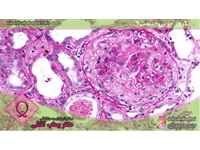

جستجو کلمه جستجو جستجو گروه بندی همه موارد مقالات » دانستنی های پزشکی زنان » پستان از تاریخ تاریخ صحیح نمی باشد. * تا تاریخ تاریخ صحیح نمی باشد. * کیست پستان چیست؟ علائم و درمان آن کیستهای پستان در واقع کیسههای پر از مایع درون بافت پستان هستند که عموماً غیر سرطانی و بیخطر هستند. این کیستها به صورت تکی یا چندتایی در سینه فرد مشا... علت ترشح از نوک پستان چیست و راههای درمان آن ترشح از نوک پستان زمانی است که از نوک یک یا هر دو بطور خود بخود و یا تحت اثر تحریک یا فشار خارجی مایع خارج شود که دلیل این ترشح همواره و الزاما نشانه ... آبسه پستان چیست؟ علائم و درمان آن آبسه پستانی که به آن ماستیت نیز گفته میشود از دیرباز یکی از مشکلات شایع مرتبط با پستانها بوده است که در بعضی از افراد در نوک پستان ظاهر شده است و هم... کلسیفیکاسیون پستان چیست و چگونه درمان میشود؟ کلسیفیکاسیون پستان رسوب کلسیم در بافت پستانی است. شامل دو نوع میکرو کلسیفیکاسیون و ماکرو کلسیفیکاسیون میشود و عمدتا غیر سرطانی و خوش خیم است. درد پستان درد پستان شایعترین شکایت در میان خانمها میباشد. این درد ممکن است در یکی یا هر دو پستان و یا زیر بغلها (اگزیلا) حس شود. اغلب این درد بصورت سنگینی و... خودآزمایی پستان چگونه است در سالهای اخیر سرطان پستان رو به افزایش گداشته است و روز به روز تعداد بیشتری از خانمها مبتلا به این نوع سرطان میشوند و به همین علت عمر آنها کوتاه م... پاپیلومای درون مجرایی چیست؟ پاپیلوما درون مجرایی یکی از انواع پاپیلوماها است که در درون مجرای شیری پستان ایجاد میشود و دارای دو نوع انفرادی و چند گانه میباشد که هر کدام دارای ن... نکروز چربی سینه چیست؟ علل ایجاد و راههای درمان آن نکروز چربی یکی از عارضههای مربوط به بافتهای مختلف بدن از جمله بافت پستان است که در بعضی از افراد دیده میشود و دلیل آن اختلال در یک آنزیم چربی میبا... همه چیز درباره ژنیکوماستی (علل ایجاد، تشخیص و درمان) بزرگ شدن سینه در مردان و پسران یا ژنتیکوماستی عارضهای است که بر اثر عوامل مختلفی ایجاد میشود. در ادامه این مطلب قصد داریم در خصوص این عارضه، علائم و... تومور فیلوئیدس چیست؟ علائم و درمان آن تومور فیلوئیدس جزء تومورهای نادر پستانی بوده واغلب در دهه 30 و 40 سن خانمها در پستان ایجاد میشود ولی در هر حال در هر سنی ممکن است بوجود آید. این توم... در مورد سرطان پستان در آقایان بیشتر بدانید آیا مردها هم سرطان سینه میگیرند؟ سوالی که بسیاری از آقایان پس از مراجعه به پزشک برای درمان بیماری خود میپرسند. در پاسخ به این سوال باید گفت اگر چه ش... انواع جراحیهای سرطان پستان جراحی سرطان پستان به دو روش ( Mastectomy) ماستکتومی و (Lumpectomy) لامپکتومی انجام میشود. تغییرات فیبروکیستیک چیست؟ بیماری تغییرات فیبروکیستیک پستان در واقع تجمع توده های غیر سرطانی و خوش خیم در بافت پستان است. فیبروکیستیک عموماً خطرناک و کشنده نیست. آیا در دوره بارداری میتوان ماموگرافی انجام داد؟ گاهی در دوره بارداری به منظور تشخیص سرطان پستان ماموگرافی انجام میشود. برای محافظت جنین از اشعه بهتر است از محافظ سربی برای پوشش استفاده شود. عمل جراحی بازسازی پستان چیست؟ طی بازسازی پستان با استفاده از عمل جراحی، پستانی با فرم و شکل جدید برای بیمار ایجاد میشود. بازسازی ممکن است پس از برداشتن همه پستان (ماستکتومی) و ی... آنچه خوب است در مورد سرطان پستان(سینه) بدانیم.(بخش اول) پستان شایعترین مکان برای ایجاد سرطان در بدن یک خانم میباشد. شیوع سرطان پستان در 50 ساله اخیر افزایش آماری قابل ملاحظهایی یافته است.در حدود 12% خانم... آنچه خوب است در مورد سرطان پستان(سینه) بدانیم.(بخش دوم) پستان شایعترین مکان برای ایجاد سرطان در بدن یک خانم میباشد. از این رو آیا تغذیه سالم میتواند شانس ابتلا به سرطان سینه را کاهش دهد؟ و آیا سیگار کشید... نمونه برداری پستان یا بیوپسی چیست؟ و انواع آن بیوپسی پستان چیست و چه کاربردهایی دارد؟ آیا نمونه برداری پستان دردناک است؟ چه مواقعی بیوپسی پستان توصیه میشود و چه مراکزی انجام میدهند؟ سونوگرافی پستان : آنچه باید پیش از سونوگرافی سینه یا پستان بدانید سونوگرافی پستان یا سونوگرافی سینه ، نوعی تصویر برداری با روش التراسوند، با هدف شناسایی توده های احتمالی موجود در بافت سینه است. تعریف پستان(BREAST ) آناتومی و بیماریهای مربوط به سینه در حال حاضر بر اساس آمارها به نظر میرسد سرطان پستان در خانمها، مهمترین عامل مرگ و میر ناشی از سرطان میباشد. آدنوزیس (Adenosis) چیست؟/ علائم و درمان آن آدنوزیس تودههای مدور کوچک و گاهی قابل لمس میباشد که بر اثر بزرگ شدن لبولهای پستان ایجاد میشوند. اگر این توده ها در محل جای زخم ناشی از عمل جراحی (... فیبروآدنوم چیست؟ علائم و درمان آن فیبروآدنوم شایعترین تودههای پستانی میباشند که سرطانی نیستند. فیبروآدنومها معمولا به تودههای بدون درد، متحرک با قوام لاستیکی در پستان گفته میشود ... چگونگی درمان ماستیت یا عفونت پستان ماستیت التهاب پستان است که باعث قرمزی، درد، احساس گرما و تورم در پستان میشود. ماستیت در شیردهی و غیر شیر دهی چیست؟ و ماستیت چگونه درمان میشود؟